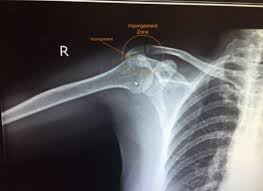

오십견은 유착성 관절낭염이나 동결견(frozen shoulder)라는 다른 이름으로 명명되어 지는데 임상적으로 볼 때 운동제한을 동반한 어깨 통증과 야간통증이 있을 때 의심하게 되는 질병으로 운동범위 검사와 어깨 MRI를 통해서 진단한다고 한다.

일반적으로 외상이나 지속적인 고정 후에 발병하지만 회전근개의 질환이나 석회성 건염 같은 질환, 또는 중풍, 심근경색, 당뇨 등에 의해 속발성으로 나타나기도 한다고 한다.

통증은 외전, 외회전, 신전시킬 때 악화되며 삼각근 부착부와 위팔의 바깥쪽으로 통증이 전해지기도 한다고 한다.